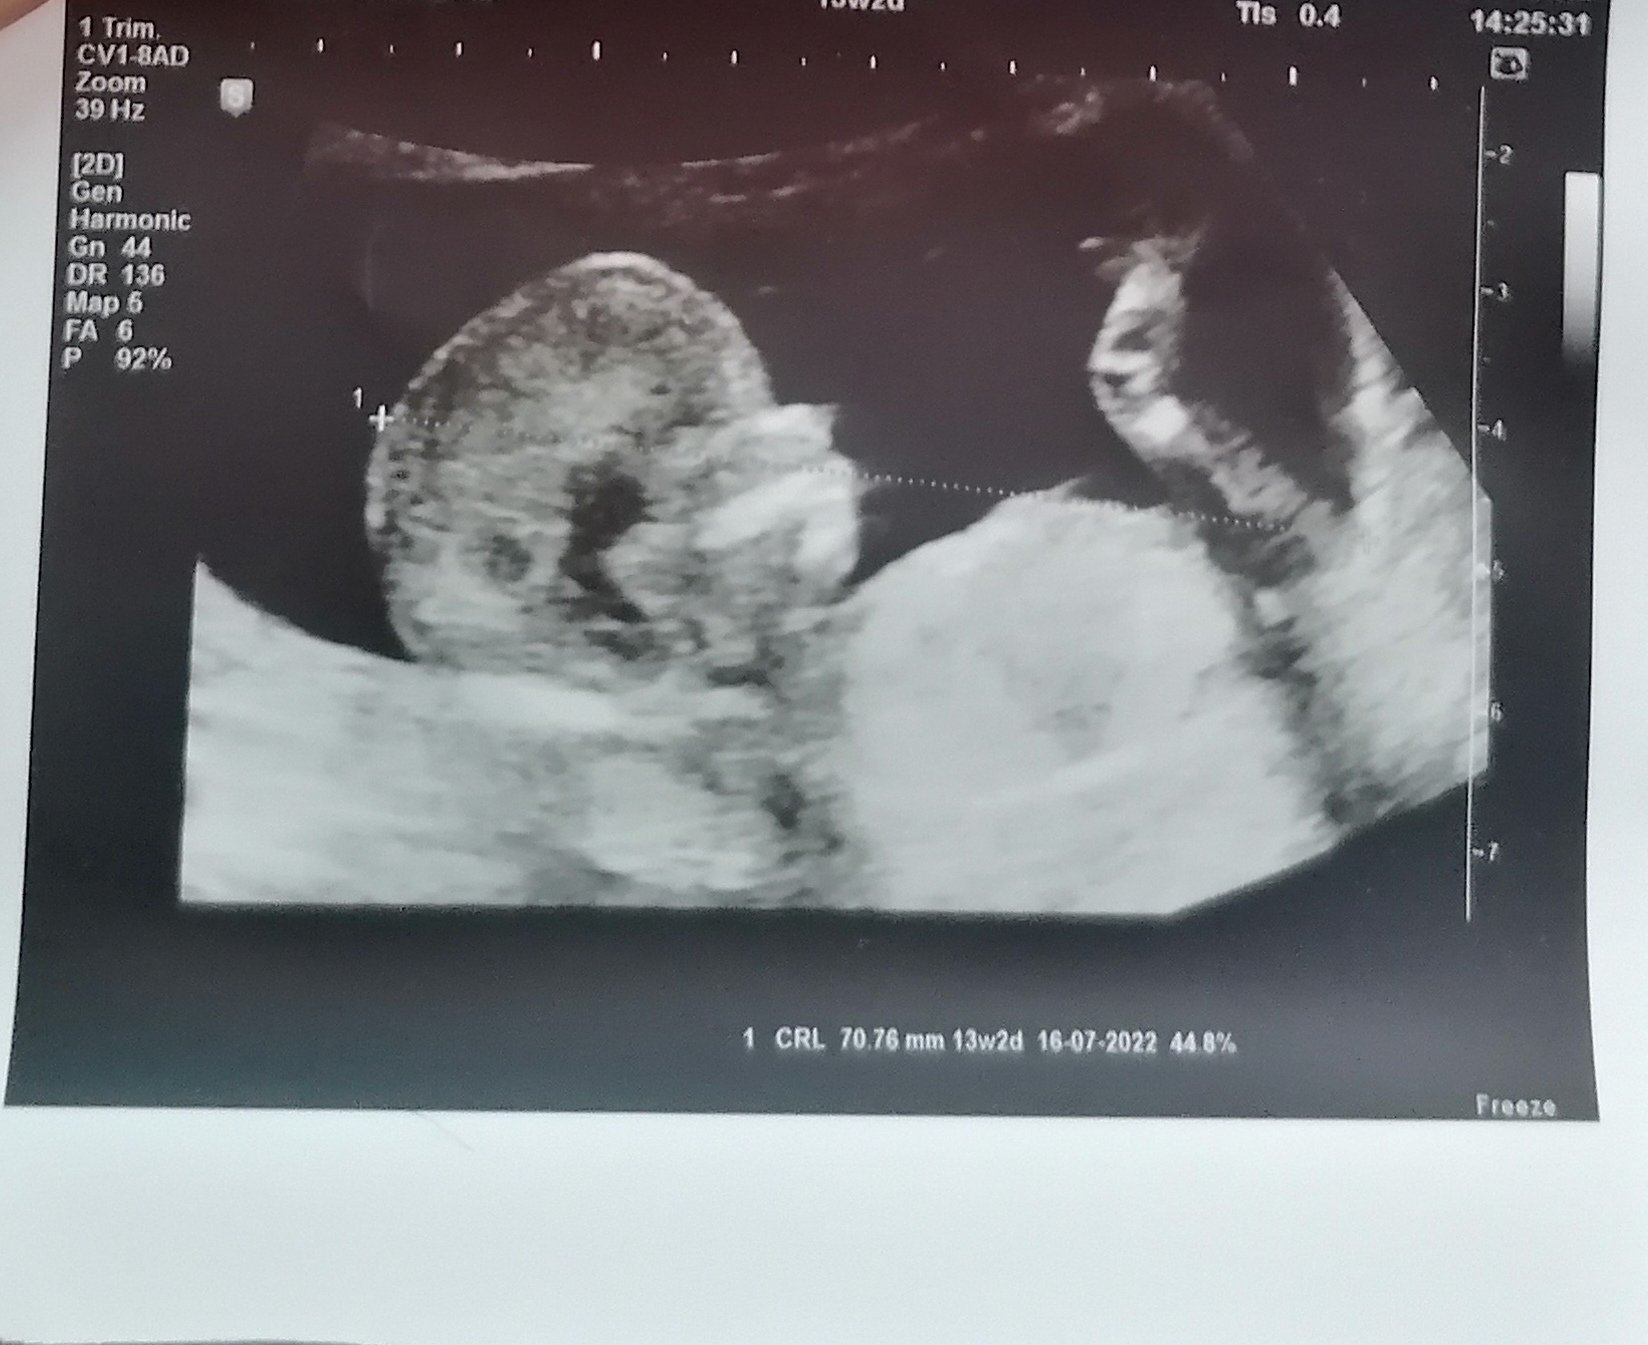

Какви изследвания се извършват по време на фетална морфология и какво може да се очаква по време на прегледа?